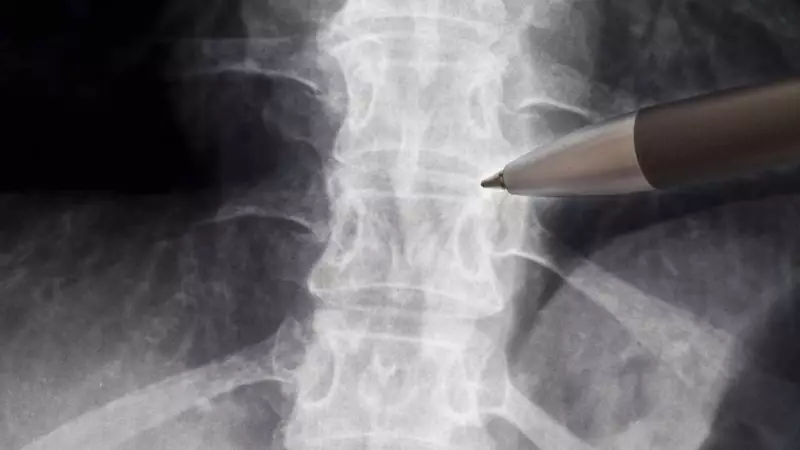

Nesta primeira fase, a pesquisa será realizada com um grupo inicial de cinco pacientes voluntários. Esses participantes devem ter lesões agudas da medula espinhal torácica, especificamente entre as vértebras T2 e T10. Um critério fundamental para inclusão no estudo é que a indicação para cirurgia tenha ocorrido em um período inferior a 72 horas após o trauma.